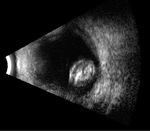

Rycina 2. Tylne odłączenie ciała szklistego bez istotnego pogrubienia kory ciała szklistego, powstałe na skutek niedawno przebytego urazu tępego. Siatkówka i naczyniówka są przyłożone